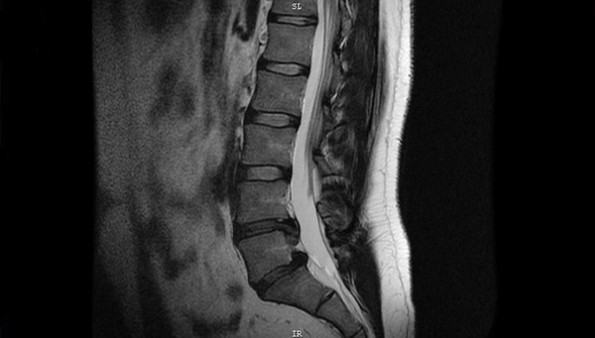

Грыжа в пояснице образуется в результате разрыва фиброзного кольца из-за повышенной физической нагрузки. Часть больного диска проникает в межпозвоночный канал и оказывает давление на нервные корешки, спинной мозг, сосудистые пучки. В результате человек страдает от сильной боли, нарушения чувствительности, патологий кровообращения, ослабления рефлекторной функции, сосудистых нарушений.

На начальном этапе развития заболевания грыжа имеет небольшие размеры (до 3 мм). Однако отсутствие адекватного лечения и неправильный образ жизни способствуют росту новообразования. В результате грыжа начинает давить на нервные корешки, что проявляется сильными болями, мышечной слабостью, парестезиями.

Рост новообразования также провоцирует компрессию вегетативных нервов, что приводит к нарушению работы органов мочеполовой системы (простатит, нарушение менструального цикла, отсутствие эрекции).

Любой дискомфорт в области поясницы – это весомый повод для обращения к доктору. Своевременная диагностика позволяет избежать развития сопутствующих заболеваний, купировать боль и уменьшить размер новообразования.